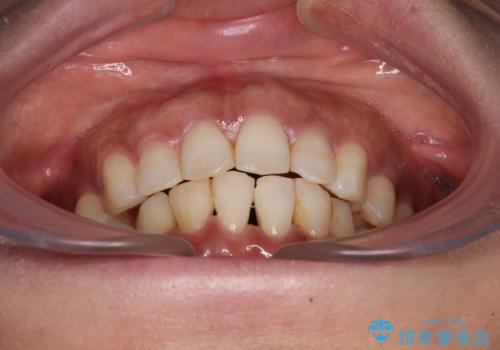

- 上下前歯のデコボコ改善をインビザラインにて行いたいとのことで来院された患者様です。

インビザラインをご希望のことで、IPR(歯と歯の間を削る)などによりスペースを獲得して、排列していくこととしました。

骨格的に上下顎が左右にずれていたため、正中位置は現状を維持したまま歯列不正を解消していくことになります。

なかなか装着時間が守れず、後戻りを繰り返しながら治療を進めたため、インビザライン治療期間期限ギリギリの5年弱の期間を要しました。